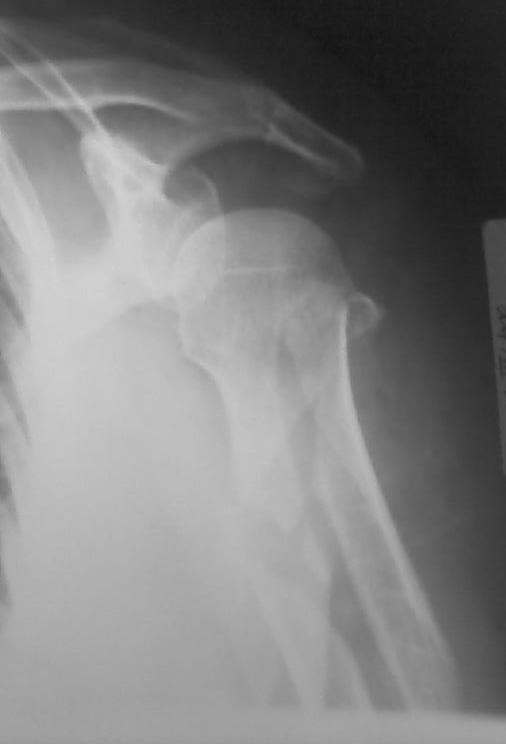

Высылаю рентгенограммы больной до операции и в гипсовой лонгете.

Сейчас больную вообщем-то особо ничего не беспокоит, незначительная

болезненность в области перелома при движениях плечом, первые два дня

была отечность кисти, которая сейчас исчезла, объем движений в

локтевом суставе постепенно увеличивается, отведение плеча пока

небольшое. Дистальное блокирование выполнено одним винтом в

передне-заднем направлении (через бицепс. Да, клинок мы конечно же

заблокировали концевым колпачком. Нас тоже беспокоит возможность

развития импиджмент синдрома, надеемся на то, что больная разработает

движения в плечевом суставе.